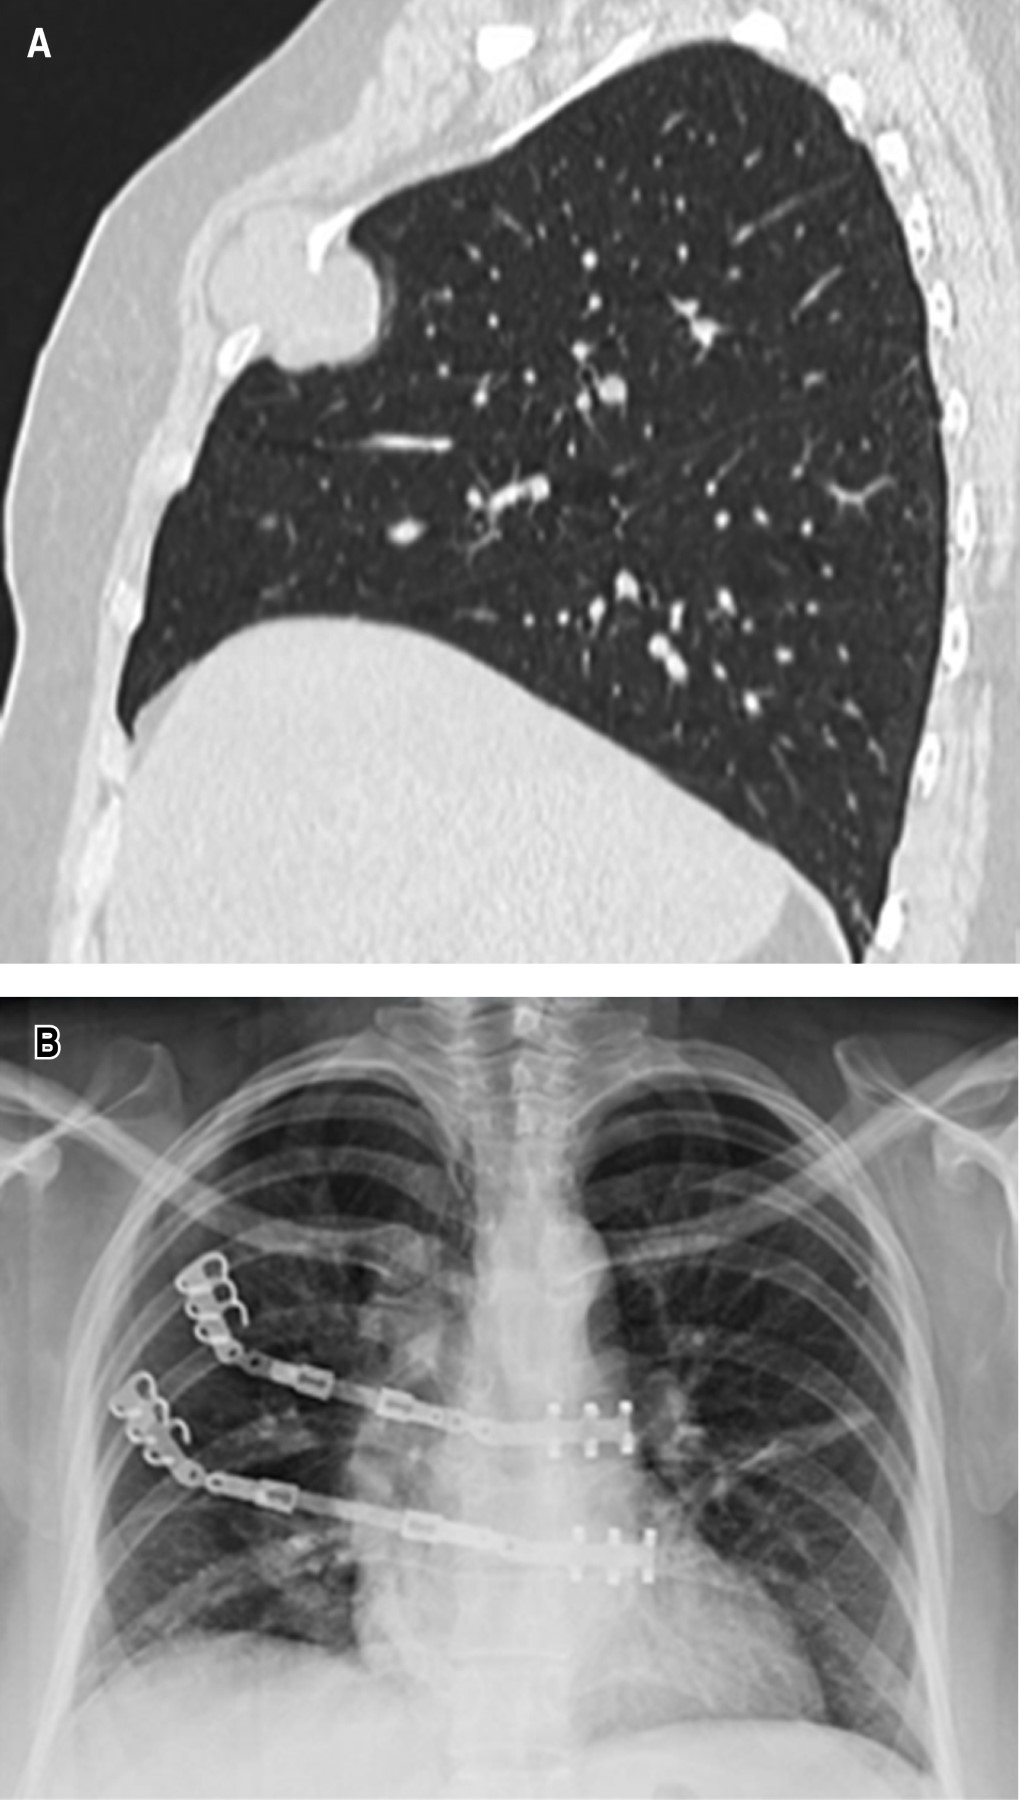

• ? Caso 4: masculino de 53 años de edad con fracturas costales izquierdas laterales (5-8) y posteriores (5-8), las cuales se fijaron con sistema StraCos® para trazos laterales y posteriores, además de fijación con tornillos de cortical del sistema Tritium® para estos últimos trazos por la cercanía con las apófisis transversas de la vértebra adyacente (Figura 4).

Figura 4